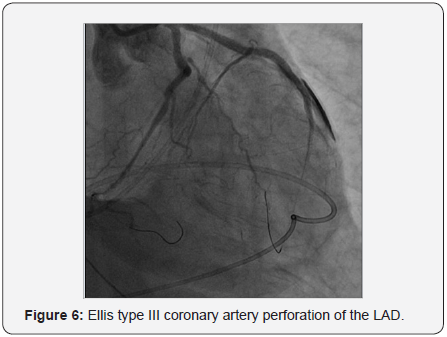

Ellis type III perforation from stented mid to distal LAD was noted as illustrated in Figure 6. Initially we used balloon inflation at the perforation site to seal the leakage. Bedside 2 Dimensional echocardiography showed acute cardiac tamponade with surrounding effusion of more than 100cc. Emergent pericardocentesis was done via subcostal approach with systolic blood pressure restored to more than 100mmHg after draining bloody effusion (250cc) from pig-tail catheter. Protamine 50mg was administered. We completed deployment of a 2.75x33mm (EES) Xience Prime DES (Abbott Vascular) at proximal to mid LCx under 5.5F guide-liner catheter support and anchoring a 3.0x15mm Hiryu (TERUMO) HPB at mid LAD at 24atm.